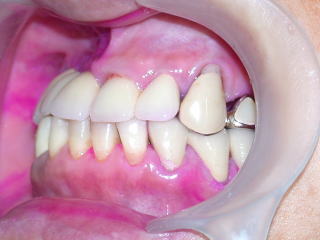

上部構造物作製、試適、調整し装着しました。

今後は1ヶ月おきにメンテナンスに来院していただき、経過を見て行きます。

患者さんは、義歯の不満が全て解除され、大変満足されており、当方も嬉しい限りです。